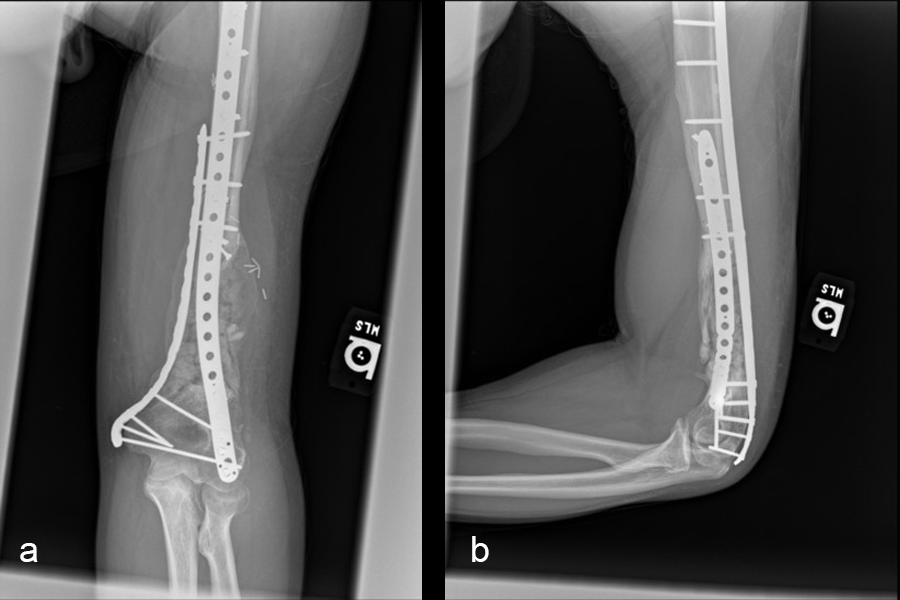

The second stage of surgery took place in October 2022. The cage was inserted (Figs 20-22) and filled with ~20cc autograft obtained by RIA of the femur, 30cc allograft and 3cc BMAC.

Healing progressed well over the following 9 months (Fig 23 - 27). The patient’s pain was well controlled in the early postoperative phase, and he was weaned off the prescribed narcotics after four weeks. He remained smoke free for the first four weeks and then admitted to re-starting his vaping. His elbow ROM improved significantly to 20-125 and good supination/pronation.